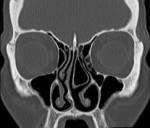

- Once I start allergy shots, I’ll never have any problems. #Allergy immunotherapy or “allergy shots” are very helpful to relieve symptoms of #hay fever such as sneezing, runny nose and even wheezing, but they don’t cure everything. For instance, if you have sinusitis, don’t count on your shots to cure your symptoms–you have to treat the sinuses for relief. This may include antibiotics/prednisone for one month at a time, or even surgical intervention. This is the reason I will often obtain a CT scan of the sinuses before starting allergy shots–to make sure I’m not missing an infection or anatomical obstruction in the sinus cavities. You wouldn’t expect the patient below to improve with allergy shots because they have a concha bullosa on the left side causing obstruction of nasal airflow. Not a good remedy for allergy shots!